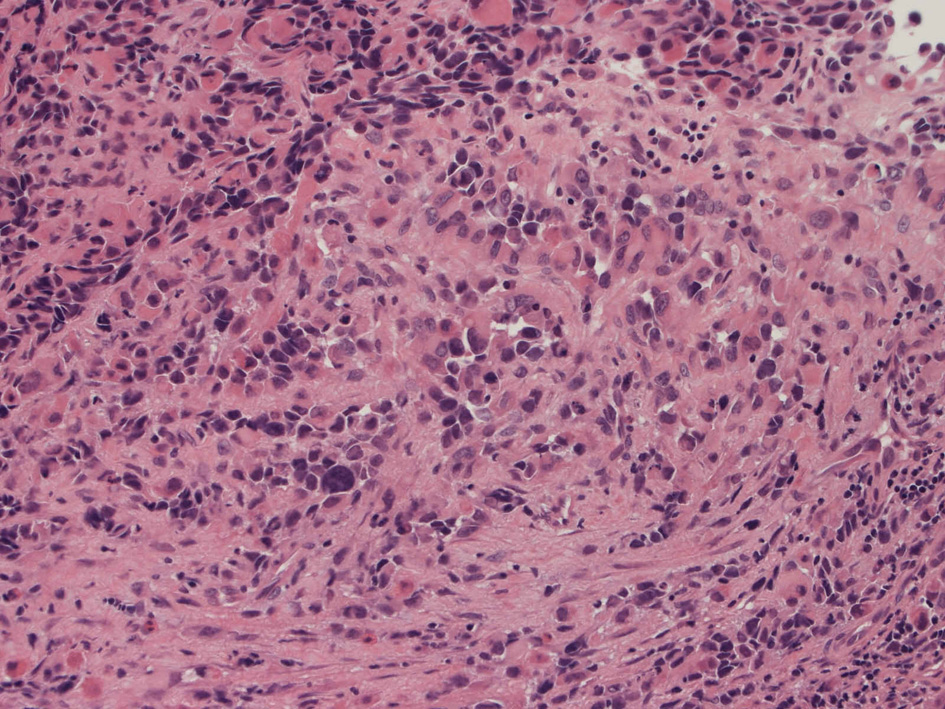

Alveolar rhabdomyosarcoma

Alveolar rhabdomyosaroma

Undifferentiated small round cell tumors of the sinonasal tract

rhabdomyosarcoma 横紋筋肉腫

40歳女性 鼻粘膜腫瘤

右頸部のしこりを自覚。近医MRIで頸部多発リンパ節腫大あり当院を紹介される。右顎下, 右鎖骨上窩にも多数のリンパ節を触れる。穿刺細胞診ではcarcinoma疑い。右鼻腔, 上顎洞にも腫瘤が認められリンパ節腫大との関係を調べるために鼻腔腫瘤の生検が行われる。

病理組織所見